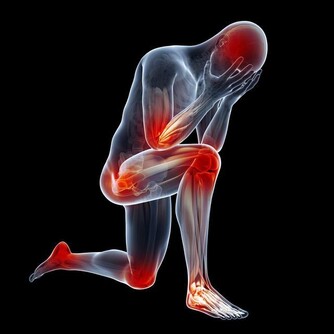

1. 他的身體某個部位很痛

雖然這種說法聽起來很寬泛,但至關重要。衰老可以欺騙男人認為“痛苦是正常的”。然而,任何一種關節疼痛都可能很快開始影響他的生活質量,背部疼痛可能會讓他特別虛弱。

更要命的是,疼痛可能是癌症的徵兆,雖然這種情況很少。但診斷疼痛的來源,將有助於讓你的身心得到休息。

比如,睾丸癌是罕見的,但在40歲以下的男性中最常見。如果他抱怨陰囊疼痛無力或感覺沉重,應該檢查一下。事實上,所有40歲以下的男性都應該進行睾丸檢查。